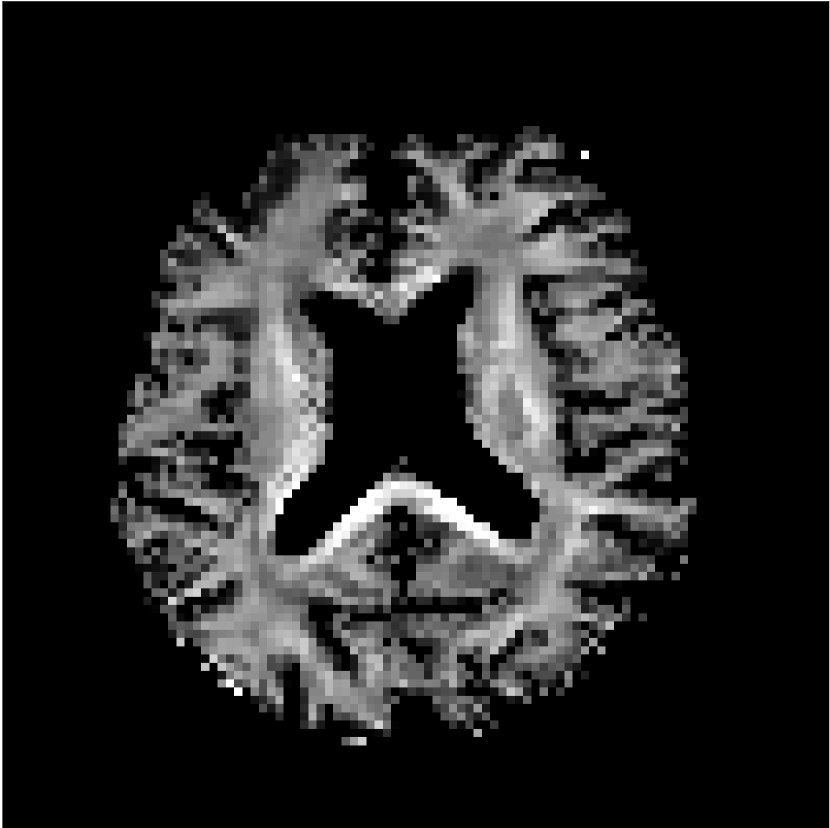

Figure 8 shows examples of non-diffusion-weighted images before and after processing. The raw images (Raw) served as the input for the magnitude deep learning (MCNN) and complex deep learning (CCNN) methods.

Raw

MCNN,

MCNN Resid.,

CCNN,

CCNN Resid.,

No PF

5/8 PF

Both methods remove artifacts, but the MCNN method allows residual rippling artifacts to pass through in the presence of partial Fourier. These rippling artifacts are not present in the CCNN method.